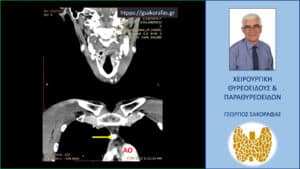

Ανάλογη με την προηγούμενη εικόνα και πάλι στην αξονική τομογραφία σε προσθιοπίσθια διατομή. Το ενδοθωρακικό αδένωμα (κίτρινο βέλος) έμπροσθεν της αορτής (ΑΟ).

Ανάλογη με την προγούμενη είκόνα και πάλι στην αξονική τομογραφία σε προσθιοπίσθια διατομή. Το ενδοθωρακικό αδένωμα (κίτρινο βέλος) έμπρσθεν΄της αορτής (ΑΟ).